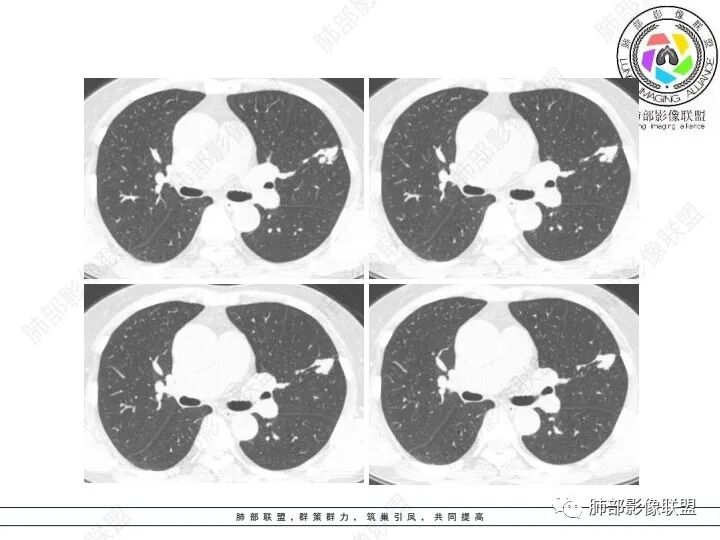

1、临床特点:61岁女性,体检发现肺结节。

2、影像特点:左肺上叶不规则病灶,冠状位、矢状位、斜状位重建显示病 灶整体沿着支气管方向呈斑片状,多结节堆积感明显,病灶大部分边缘显示平直,局部边缘稍膨隆,边界显示比较清楚,近端支气管壁显示增厚,周围可见长索条影及多发结节影,未显示典型“树芽征”。邻近叶间裂未受牵拉凹陷。纵隔窗显示病灶中央可见点状高密度钙化影。

3、病例小结:老年女性体检发现肺部结节,缺乏临床表现,需要警惕恶性。结合影像特点,左肺上叶病灶整体缺乏膨隆感,边缘大多平直,周围多发卫星灶(可见多发长索条影、并非肺CA的细短毛刺),病灶收缩力很弱(邻近叶间裂未见明显凹陷),观察1mm重建图亦可以发现病灶周围没有边界清楚的GGO,病灶内可见钙化点,肺门纵隔未见肿大淋巴结。综合以上,此病灶首先考虑炎性,结核可能性大,有条件可以增强扫描,有助于我们进一步判断。